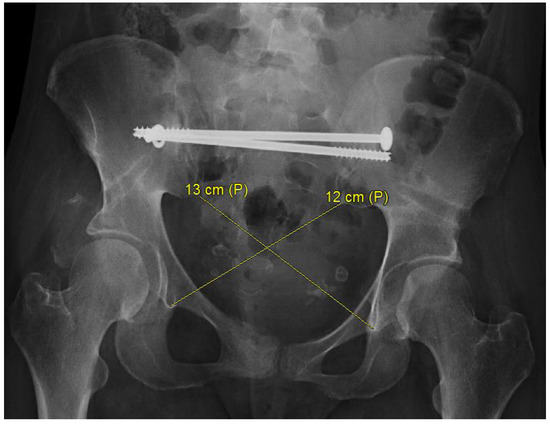

- Herteleer, M.; Thüroff, J.; Rommens, P.M. Single stage reconstruction of a neglected open book pelvic injury with bladder herniation into the upper thigh: A case-report. Arch. Orthop. Trauma Surg. 2021, 141, 855–859, Correction in Arch. Orthop. Trauma Surg. 2021, 141, 1629. [Google Scholar] [CrossRef]